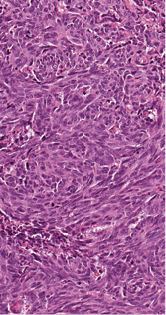

3 pav. Pancitokeratinų ekspresija visame navike ir ryškėjanti diskohezija „rabdoidiniame“ komponente (viršuje, dešinėje pusėje)

Imunohistocheminio profiliavimo metu nustatyta stipri difuzinė PanCK reakcija visuose komponentuose (3 pav.) ir menka, tačiau definityvi MUC2 žarninio tipo mucinų produkcija (4 pav.) kartu su tipiška KRAS geno 12-o kodono mutacija 2-ame egzone leistų klasifikuoti naviką kaip aukšto laipsnio (blogai diferencijuotą) adenokarcinomą. Ieškant biologinio pagrindo neįprastai naviko morfologijai paaiškinti atliktos papildomos imunohistocheminės reakcijos: Hep-Par1 (neigiama), INI1 (praradimo nėra), BRAF (neigiamas, tikėtina, nemutuotas), PMS2 ir MSH6 (reakcija išlikusi, nėra mikrosatelitų nestabilumo audinyje požymių), visose naviko ląstelių populiacijose patvirtintas jau biopsijoje identifikuotas difuzinis neuroendokrininis fenotipas (100 % Synaptophysin ir 95 % Chromogranin A ekspresija (5 pav.)). Ki67 proliferacinis aktyvumas buvo heterogeniškas ir rabdoidinės išvaizdos komponente siekė 90 proc., o likusiuose buvo perpus žemesnis (6 pav.).